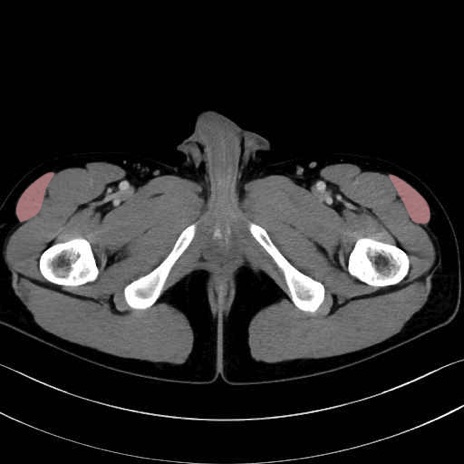

大腿筋膜張筋 (Tensor fasciae latae)